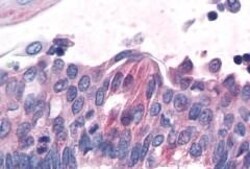

Invitrogen™ TAS1R1 Polyclonal Antibody

Putative taste receptor. TAS1R1/TAS1R3 responds to the umami taste stimulus (the taste of monosodium glutamate) and also to most of the 20 standard L-amino acids, but not to their D-enantiomers or other compounds. Sequence differences within and between species can significantly influence the selectivity and specificity of taste responses. Expressed strongly only in fungiform papillae.

| Immunohistochemistry (Paraffin) | |

| Synthetic 16 amino acid peptide from 3rd cytoplasmic domain of human TAS1R1. | |

| Human, Canine, Bovine, Pig, Horse | |